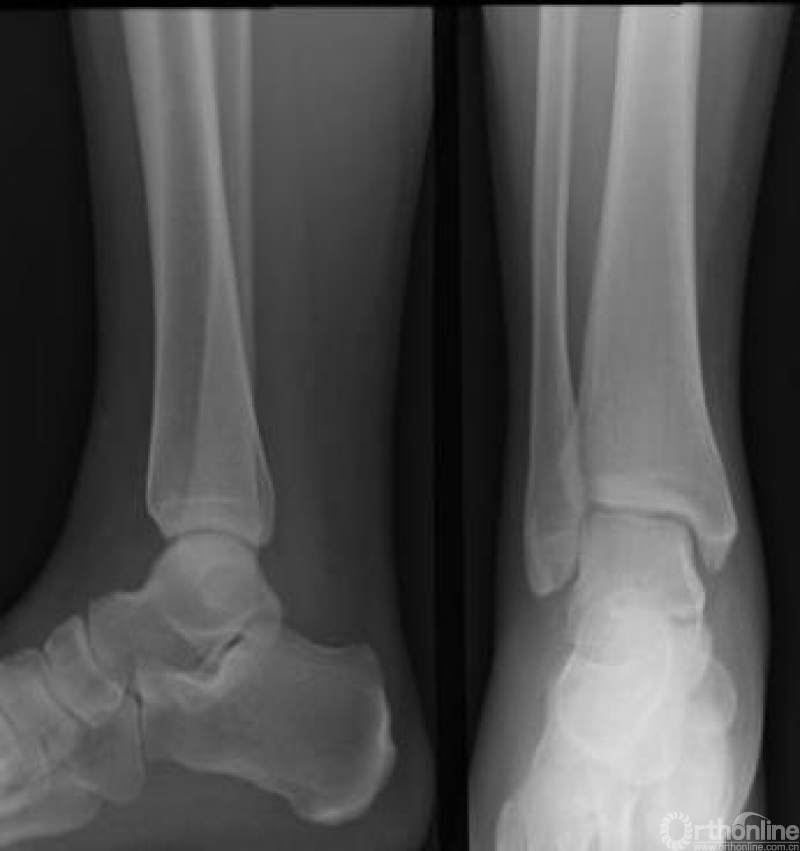

踝关节受损伤后存在压痛点或者不能够负重是行X线检查的最佳适应证。X线检查可观察有无骨折和关节间隙的改变。踝关节常规照片包括前后位、侧位以及内旋位X线片(图1)。

图1 正常踝关节正、侧位X线片